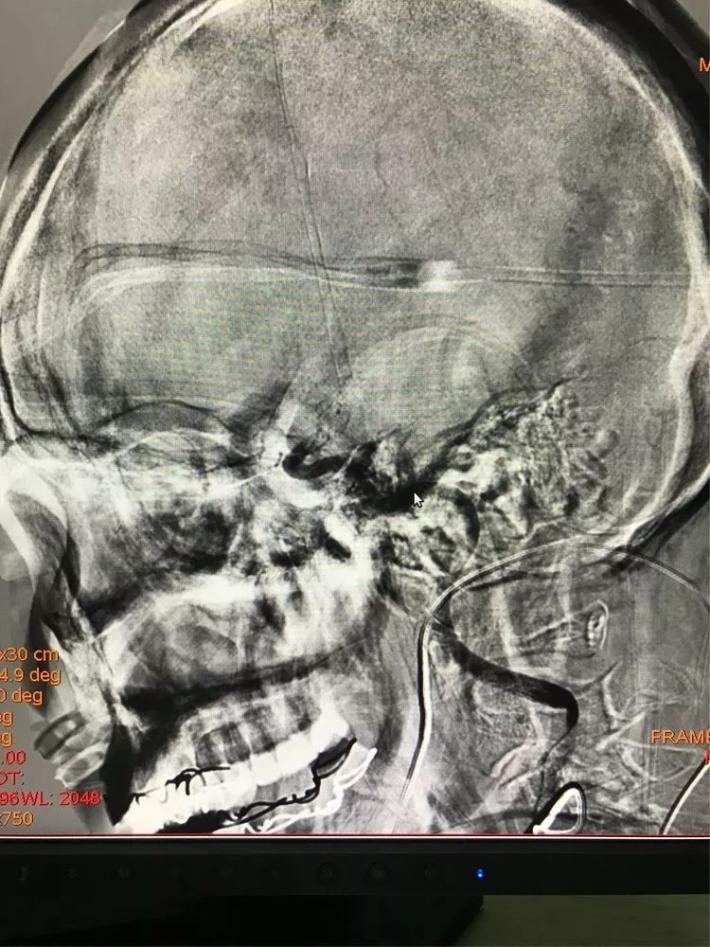

手术步骤

微导管进入大脑中动脉远端真腔。

置入支架,见大脑中动脉有血流。

取出支架,血管未开通。

再次上微导管。

微导管进入大脑中动脉远端真腔。

第二次置入支架取栓。

血管仍未开通。

第三次上微导管。

再次置入支架取栓。

见血管再通。

支架和取出来的血栓。